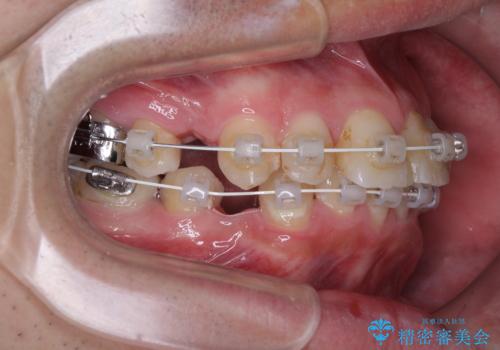

- 矯正装置

- 審美装置

- 口元の突出感と奥歯の咬み合わせの悪さを気にして来院された患者様です。

口元はやや突出感があったため、上下左右の第一小臼歯4本を抜歯してワイヤー矯正にて抜歯矯正を行うこととしました。

また、左右ともに最後臼歯が交叉咬合になっており、外側に飛び出している上顎の最後臼歯を補助装置を利用して、積極的に内側に引き込むようにしました。